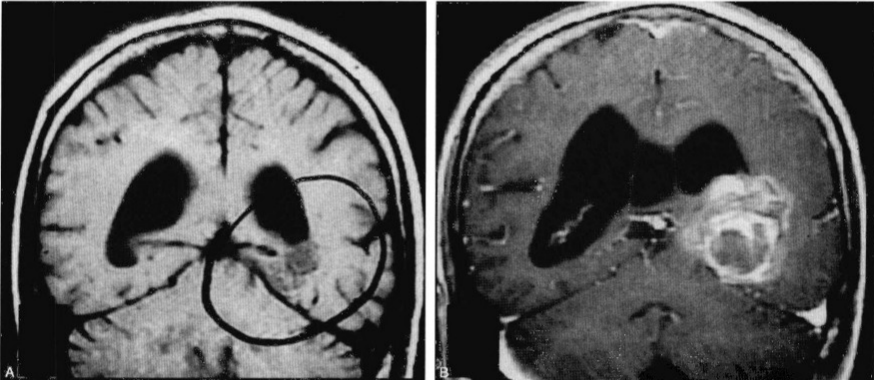

图1:此患者一直以来随访一个左侧题枕内侧的海绵状血管瘤。有头痛但无其他不同症状。(A)原来的MRI扫描发现一个2cm大小的病灶,无新近出血的证据。(B)在随访中,病灶内出血增大。钆增强冠状位MR扫描发现一在颞枕内侧面一有分割的出血性病灶,在侧脑室体部的下方,伴有脑积水。此患者予以行脑室-腹腔分流及通过颞下沟行病灶切除

脑海绵状血管瘤常会因非特异性或无关症状而做影像学检查时被发现(图1)。头痛可能反映病灶的隐匿性出血。无临床出血史患者的年出血率在0.39%~0.6%。这个发生率比动静脉畸形出血的比例低。CM的一开始出血很少危及生命,但常常引起明显症状。患者可能会完全恢复,但也可能恢复不完全。如单纯从预防出血角度进行治疗,应充分考虑影响出血的危险因素及其后果。一个重要因素是患者年龄,根据每年的出血概率统计累积后,年轻患者出血风险在其生存期内较高;另一个因素为性别,多项研究表明,女性发生出血的机会较大,是在孕期,但其他研究没有支持这种观点。